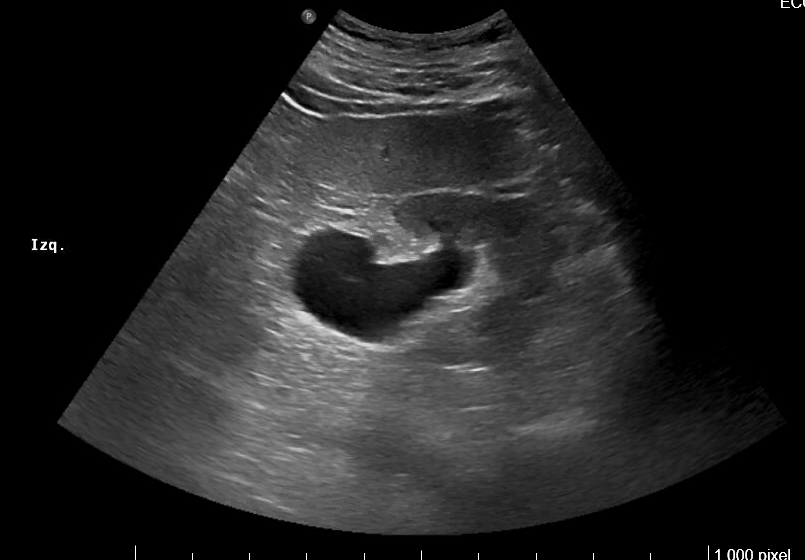

Imagen 4. Ecografía de vejiga y próstata: Corte sagital. Vejiga distendida con paredes engrosadas. Crecimiento del lóbulo medio prostático que impronta en vejiga. Volumen aproximado de 127 cc.